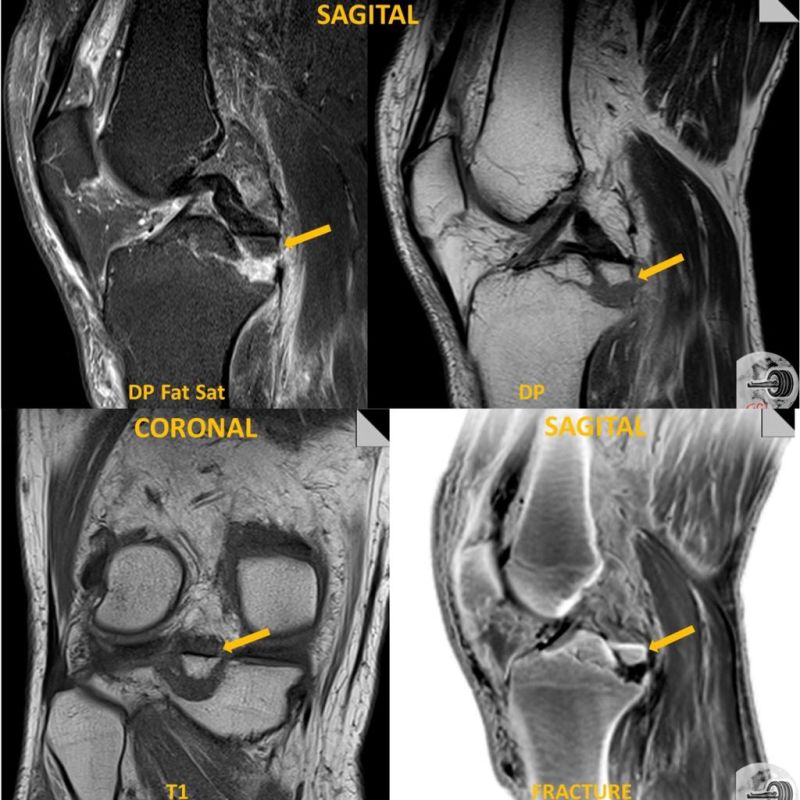

A **Técnica FRACTURE** (ou Black Bone) é uma sequência de RM adaptada que oferece alta resolução óssea, tradicionalmente vista apenas na Tomografia Computadorizada (TC). Para o operador, dominar a física e as variáveis dessa sequência de Gradiente de Eco (GRE) 3D é o segredo para o sucesso diagnóstico. FRACTURE é um acrônimo para: **F**ast **F**ield echo **R**esembling **A** **C**T **U**sing **R**estricted **E**cho-spacing.

💡 Objetivo FRACTURE: Combinar a alta resolução óssea da TC com a excelente diferenciação de partes moles da RM, sem o uso de radiação ionizante.

Para construir a sequência (que pode ser chamada de **Black Bone**, **Bone VIBE** ou **T1-SPGR/FFE** otimizado, dependendo do fabricante), o operador deve focar nos seguintes parâmetros:

Supressão de Gordura Opcional (Recomendado) Suprime o sinal brilhante da medula óssea, aumentando o contraste com o osso cortical (preto).